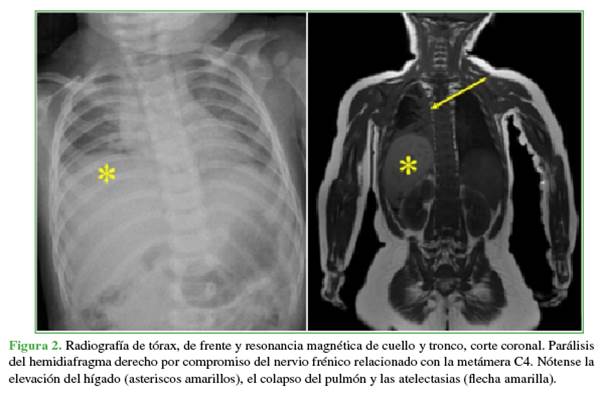

En las radiografías anteroposterior y de perfil, de columna cervical, no se observaron anomalías. El trazado de las cuatro líneas sagitales recomendadas en el trauma era normal. Sin embargo, la relación facetaria C2-C3 era dudosa (Figura 1). La disminución de la entrada de aire en el hemitórax derecho se relacionó con una parálisis diafragmática y atelectasia pulmonar masiva (Figura 2). La RM de columna cervical y base del cráneo reveló una epifisiólisis del axis, una lesión ligamentaria posterior y un importante edema perivertebral (Figura 3).